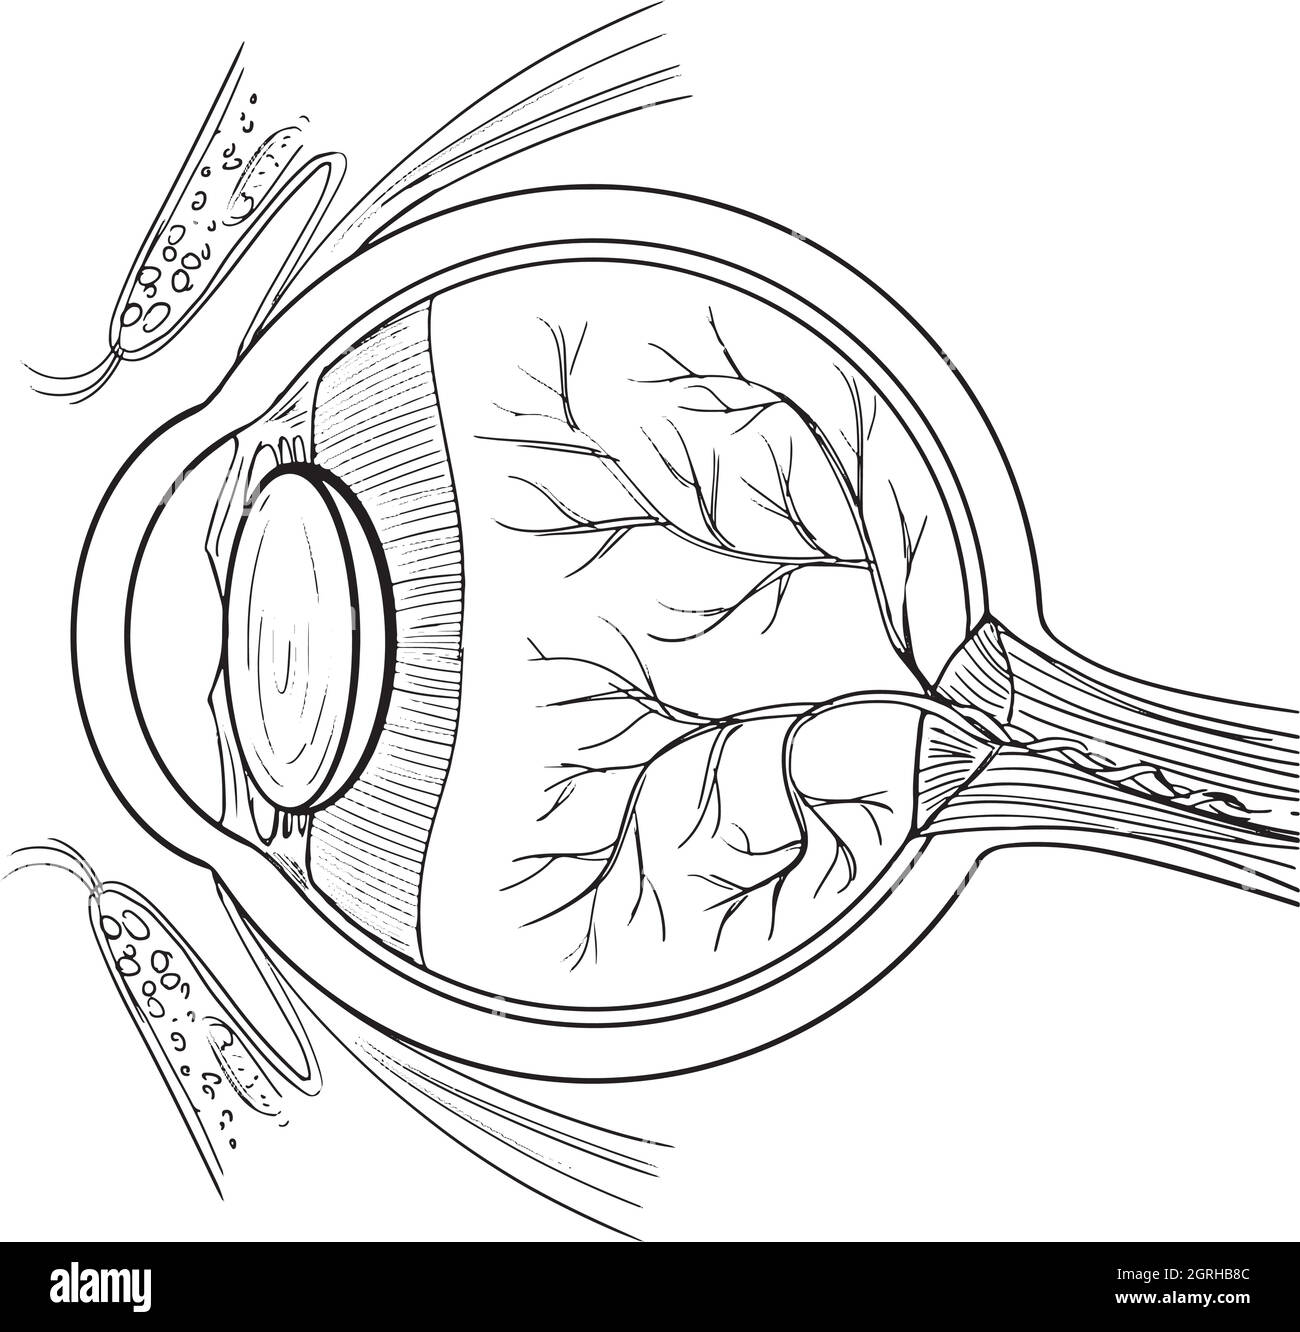

Anatomy of the human eye Stock Vectorhttps://www.alamy.com/image-license-details/?v=1https://www.alamy.com/anatomy-of-the-human-eye-image444778332.html

Anatomy of the human eye Stock Vectorhttps://www.alamy.com/image-license-details/?v=1https://www.alamy.com/anatomy-of-the-human-eye-image444778332.htmlRF2GRHB8C–Anatomy of the human eye